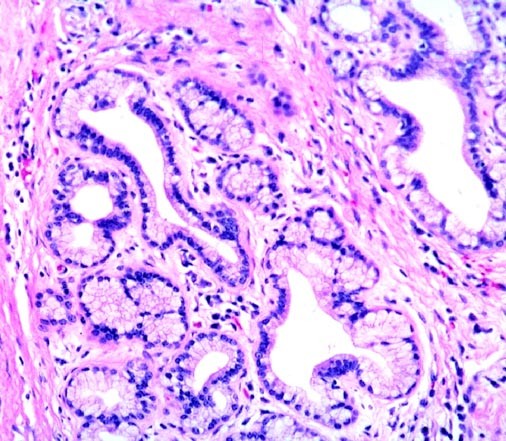

FIGURE 2

Metaplastic pyloric type epithelium has replaced part of the normal biliary epithelium of these intramural glands.